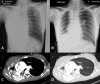

Bronchial stenosis is known to complicate endobronchial tuberculosis despite medical therapy. It is often associated with dyspnoea. In severe cases, bronchial stenosis results in airflow obstruction, impaired secretion clearance, and can lead to respiratory failure. We present an unusual observation of platypnoea-orthodeoxia syndrome in a young woman with acute atelectasis due to post-tuberculosis bronchial stricture. Imaging revealed complete middle and right lower lobe atelectasis with a partially aerated right upper lobe. In the sitting posture, there was positional worsening of dyspnoea associated with an increase in the alveolar-arterial oxygen gradient and shunt fraction. The likely mechanism was due to gravitational difference in ventilation-perfusion matching. The platypnoea-orthodeoxia syndrome was reversible following balloon dilatation of the bronchial stenosis and expansion of the collapsed lung.